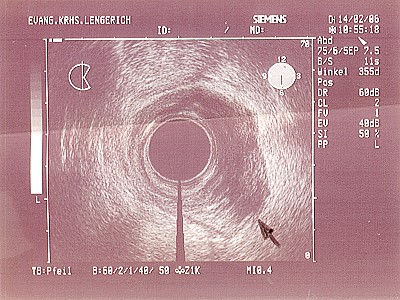

Abb. 1: Bei dem Befund ist die muskuläre Schicht des Mastdarmes nicht durchbrochen, so dass hier von einer recht guten Prognose auszugehen ist. Abb. 1: Bei dem Befund ist die muskuläre Schicht des Mastdarmes nicht durchbrochen, so dass hier von einer recht guten Prognose auszugehen ist.